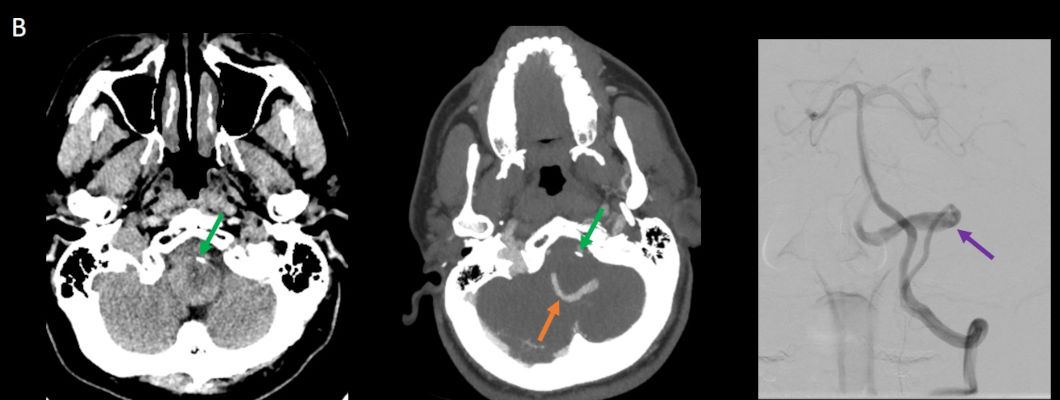

- B. Kontrastsız BT incelemede heterojen dansitede, perferinde kaba kalsifikasyon gösteren kitle lezyonu (ok), BT anjiografi MIP aksiyal kesitte yılan gibi eksantrik bir açık damar görülmektedir (ok). Sağ posterior inferior serebellar arterden (PICA) doluş gösteren tortiyoze dilate vasküler yapı (ok) DSA’ da demonstre edilmiş.

- BT

- Heterojen yoğunlukta, yuvarlak veya oval kitle lezyonları olarak görülür.

- Kısmen tromboze oldukları için, lezyon içinde farklı evrelerde kan ürünleri izlenebilir.

- BT anjiyografi (BTA) ile anevrizma içindeki patent, serpantin damar kanalı ve anevrizmanın besleyici damarları daha net bir şekilde görüntülenebilir.

- Kitle etkisi ve çevre dokularda ödem de BT’de görülebilen bulgulardandır.

- DSA

- Serpantin anevrizmaların tanısında altın standart olarak kabul edilir.

- Anevrizmanın şeklini, giriş ve çıkış noktalarınıen net şekilde gösterir.

- DSA’da anevrizma içindeki tortuöz damar kanalının morfolojisi, bir simite (“pretzel işareti”) benzetilmiştir. Bu bulgu, anevrizmanın dinamik yapısını ve içindeki kan akışınıgörselleştirmek için kritik bir bulgudur.